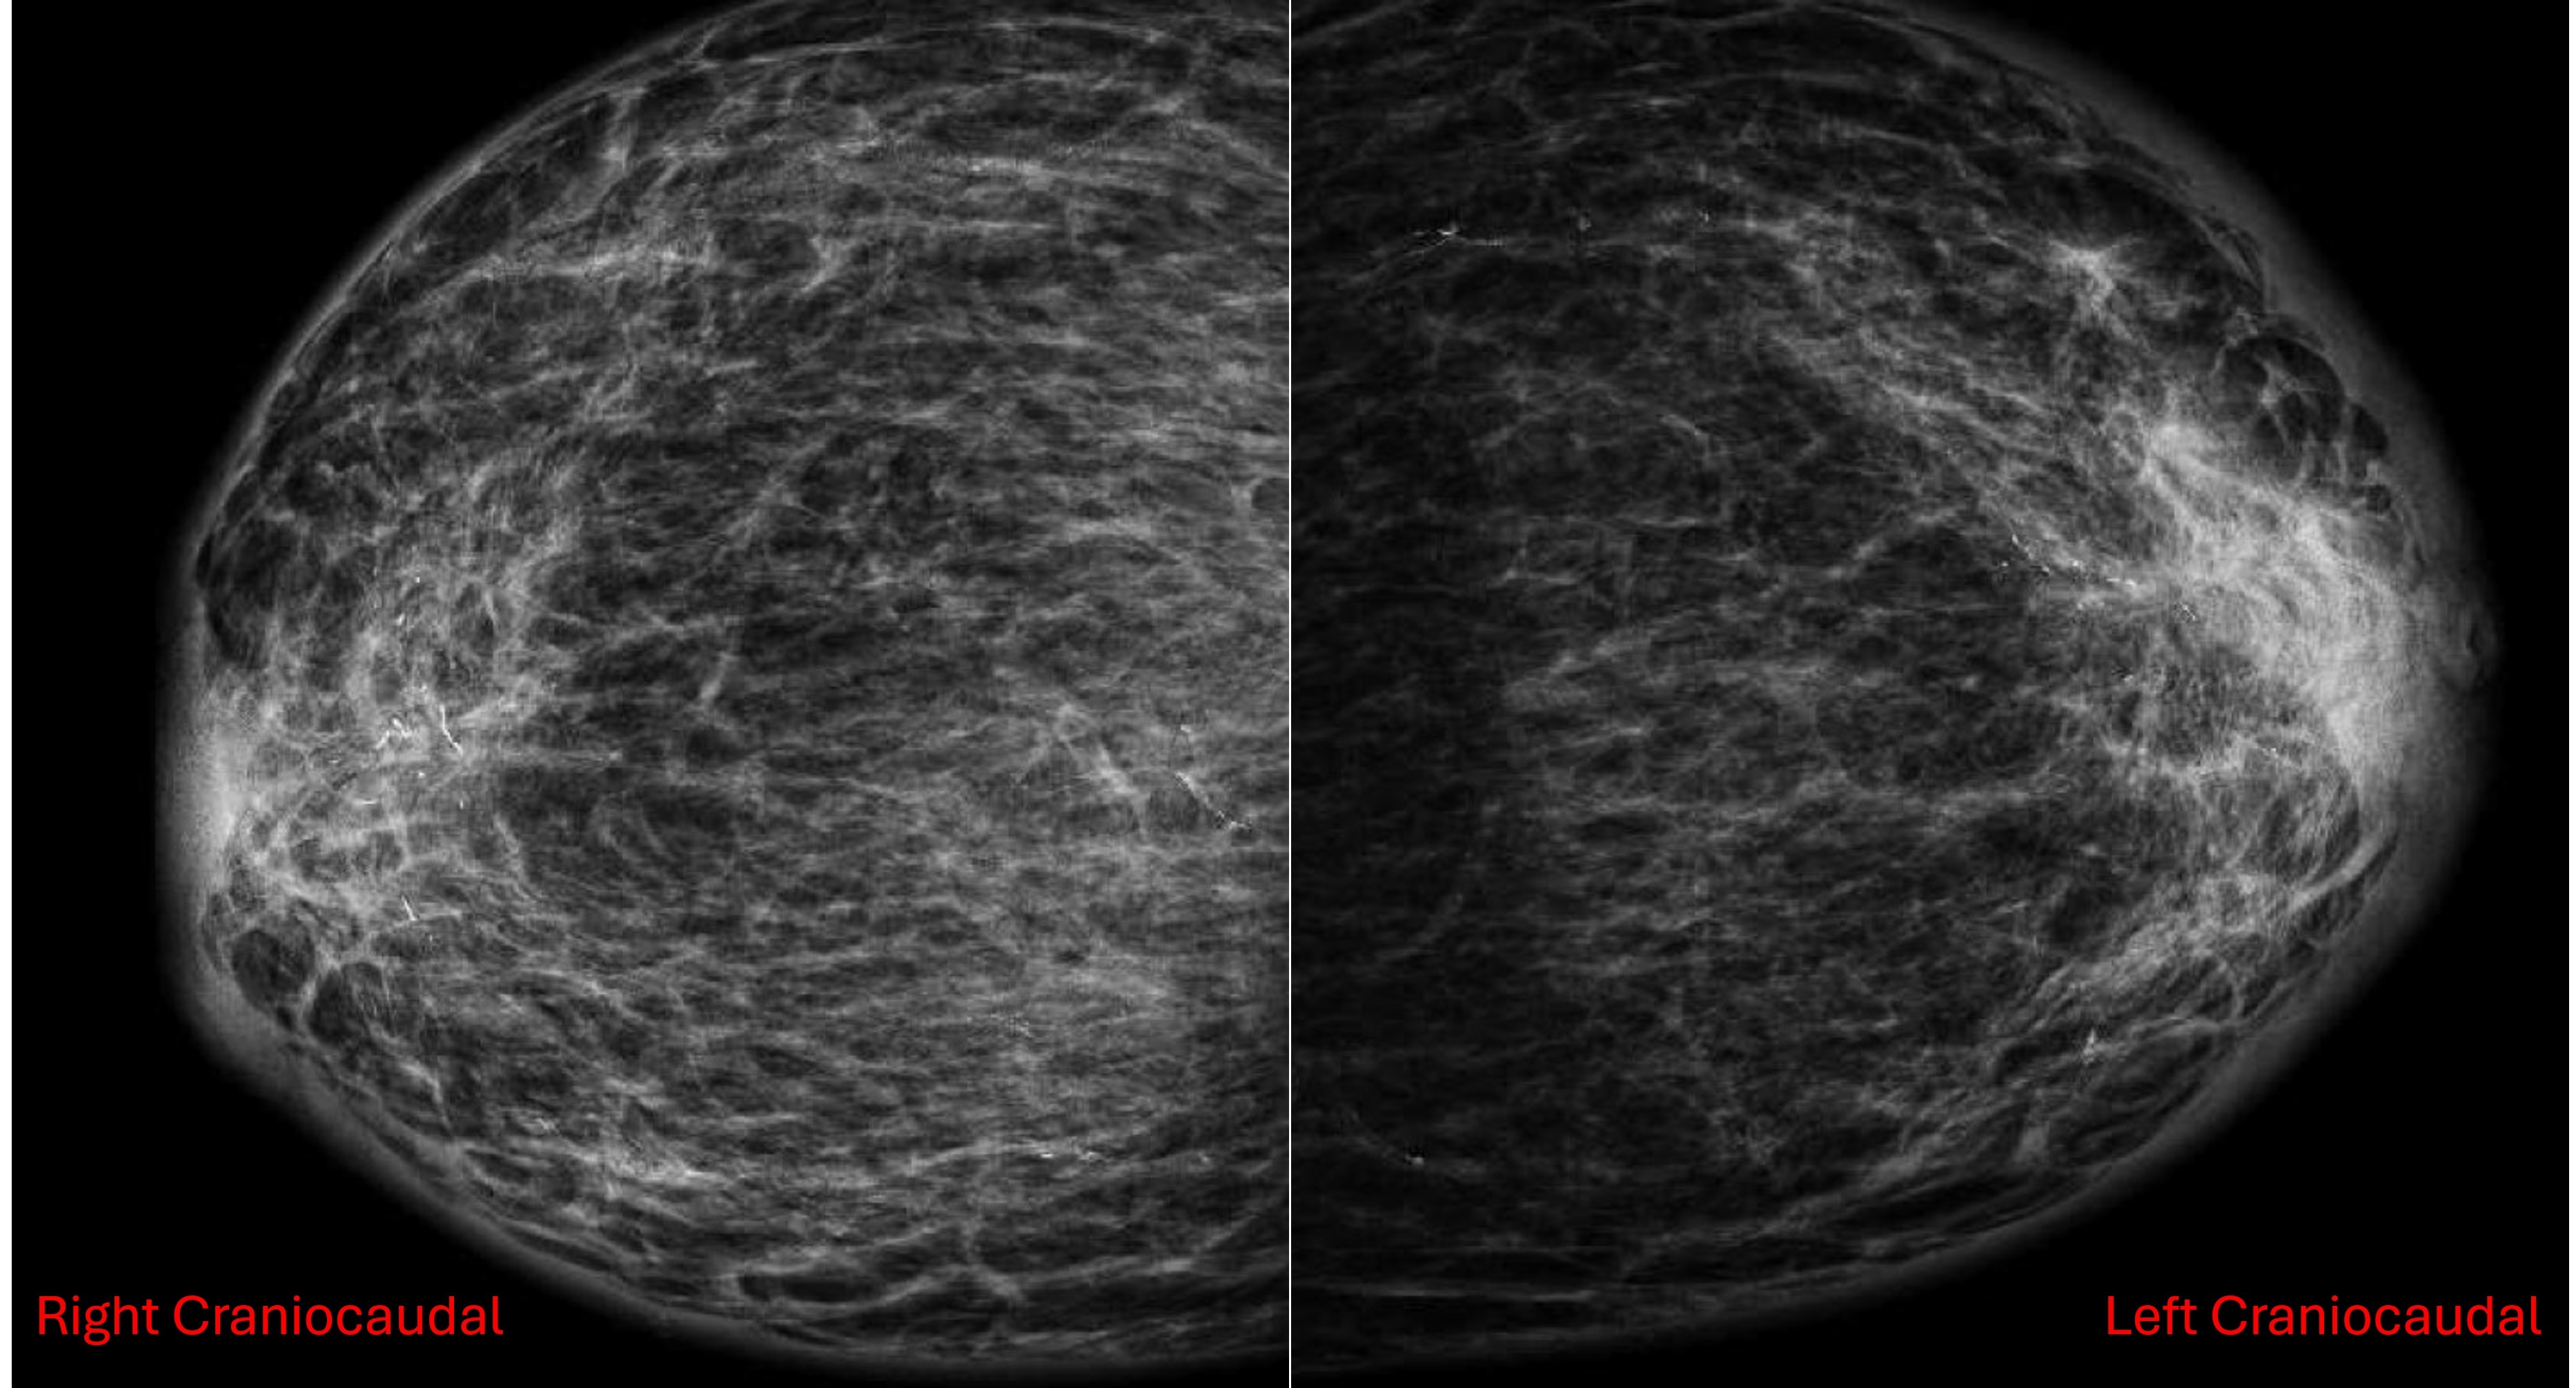

Case Presentation: A 77-year-old female presented with acute onset bilateral breast enlargement, tenderness, and erythema, along with symptoms of CHF exacerbation including dyspnea, orthopnea, and lower extremity edema. Physical examination revealed markedly enlarged, tender breasts. Imaging studies including mammography (Figure 1: Right and left craniocaudal views; Figure 2: Right and left mediolateral oblique views) and breast ultrasound showed diffuse skin and subcutaneous edema without evidence of infection or malignancy. Echocardiography confirmed reduced ejection fraction and diastolic dysfunction. Skin biopsy findings were consistent with CHF-related changes. The patient's symptoms improved with diuresis and optimization of guideline-directed medical therapy for heart failure.